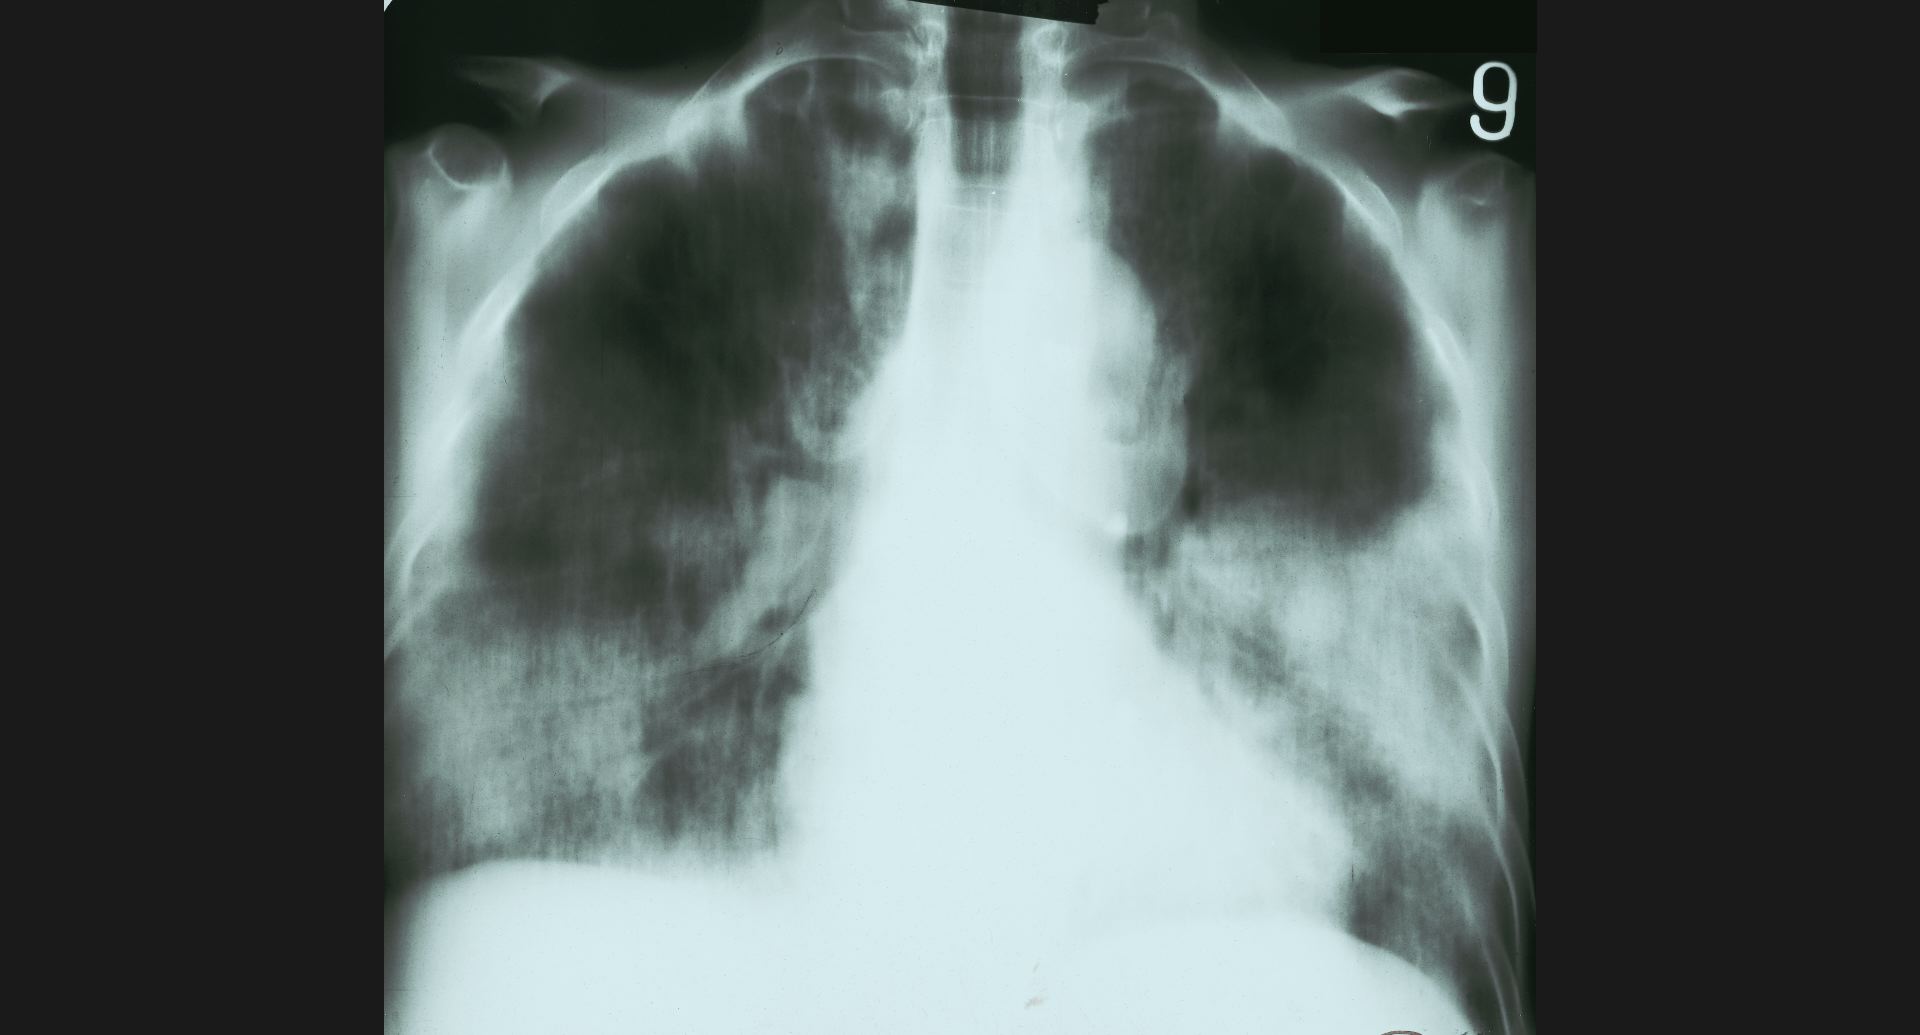

fig.9(94KB) :Pneumoconiosis

細かい斑状陰影。